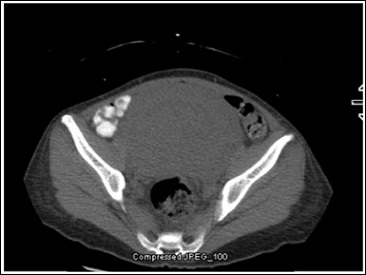

A 40-year-old female with past medical history of a large unrepaired ventricular septal defect causing severe PAH and right to left shunting (Eisenmenger’s syndrome) and a massive uterine fibroid disease (Figure1) presented to our hospital with complaints of pelvic pain which was progressively worsening, associated with palpitations and increasing shortness of breath. Six months prior to presentation she had been well, able to hike and enjoy an active lifestyle. Two months prior to presentation she became bed-bound due to severe pelvic pain. She had sought consultation at multiple other hospitals and was told that she was not a surgical candidate. She had been followed for several years for PAH in another state. She was taking riociguat, macitentan and subcutaneous treprostinil at the time of presentation.

Figure 1: CT A/P transverse view showing uterine fibroid.

Note: Transverse section of Pelvis showing massive uterine fibroid.